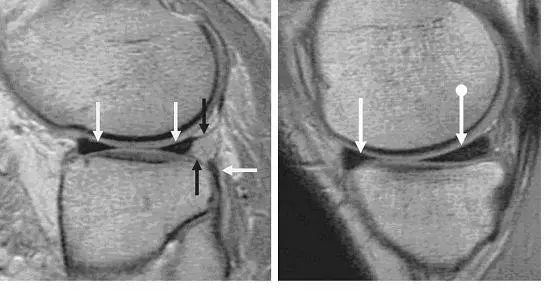

图 2 正常半月板

左图:外侧半月板,由于横截面面积一致,故在MRI 上可见外侧半月板前后角(纵向白色箭头)形状和大小较相似。上下腘肌半月板纤维束(黑色箭头)在外侧半月板后角处,形成裂孔,中间有腘肌腱(水平白色箭头)通过。右图:内侧半月板,可见后角(白色圆箭头),略大于前角(白色直箭头)